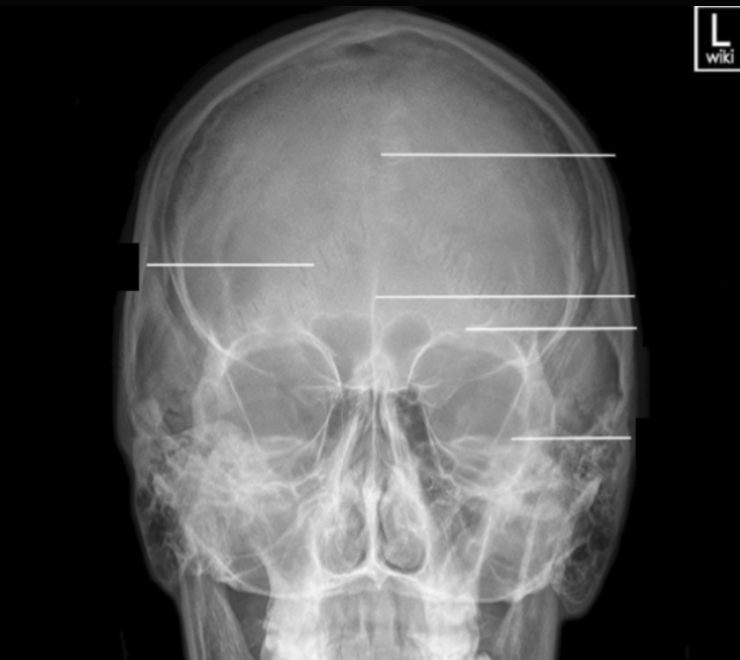

Please label